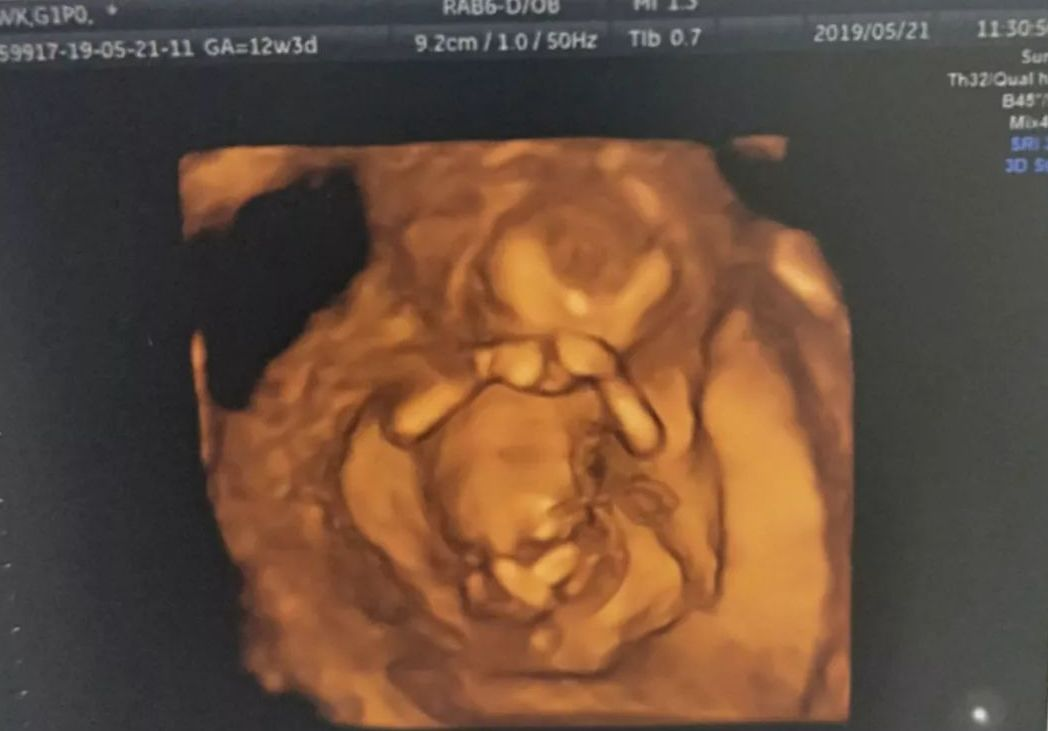

终于见到你!准爸妈们在四维彩超的镜头下,清晰的看到了宝宝!

看!这是宝宝的小手!这是他的鼻子!看到宝宝的一瞬间,爸妈们都激动起来!

四维彩超能够显示宝宝的实时动态活动图像,通过超声探头,

可以看到胎儿的眼睛、鼻子、嘴巴……宝宝伸出小手,好像在跟妈妈打招呼,继而咧嘴微笑。

当这个画面出现在彩超屏幕上时,妈妈和宝宝通过影像无声地交流,也是在出生前的第一次相遇。

这份感动,将会用图片和视频记录下来,成为宝宝和妈妈最珍贵的纪念日。